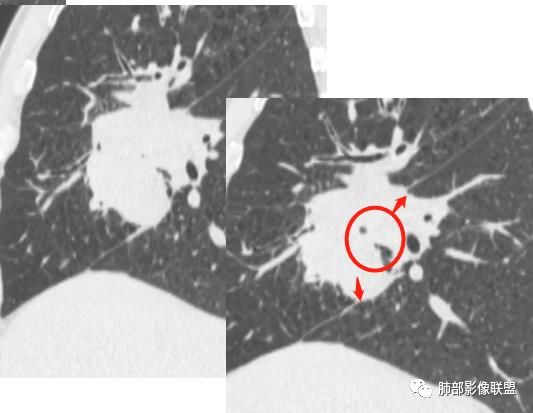

@吴婧南京市第一医院?吴老师 上叶部分有毛刺,中叶下叶部分有没有毛刺

找一下支气管,

上叶支气管没有找到,是没有给还是真的堵了

支气管有阻塞有推挤

中叶支气管还再,推移加堵塞,但是推移为主,我觉得肯定不是中叶的中央起源

下叶也都在

我现在想知道上叶支气管是全部堵了还是没有给都图片。如是没有堵塞,就是外向内的腺癌或间叶来源,如果上叶堵了,就不一样

因为中叶和下叶支气管没有堵塞为主,是外向内的迹象,现在我就是上叶图片的问题

我也是看到支气管似乎没有堵塞,除外鳞癌

外侧段是推移为主

Coke with ice:

外侧段截断了

堵塞得不适外侧段,是内侧段